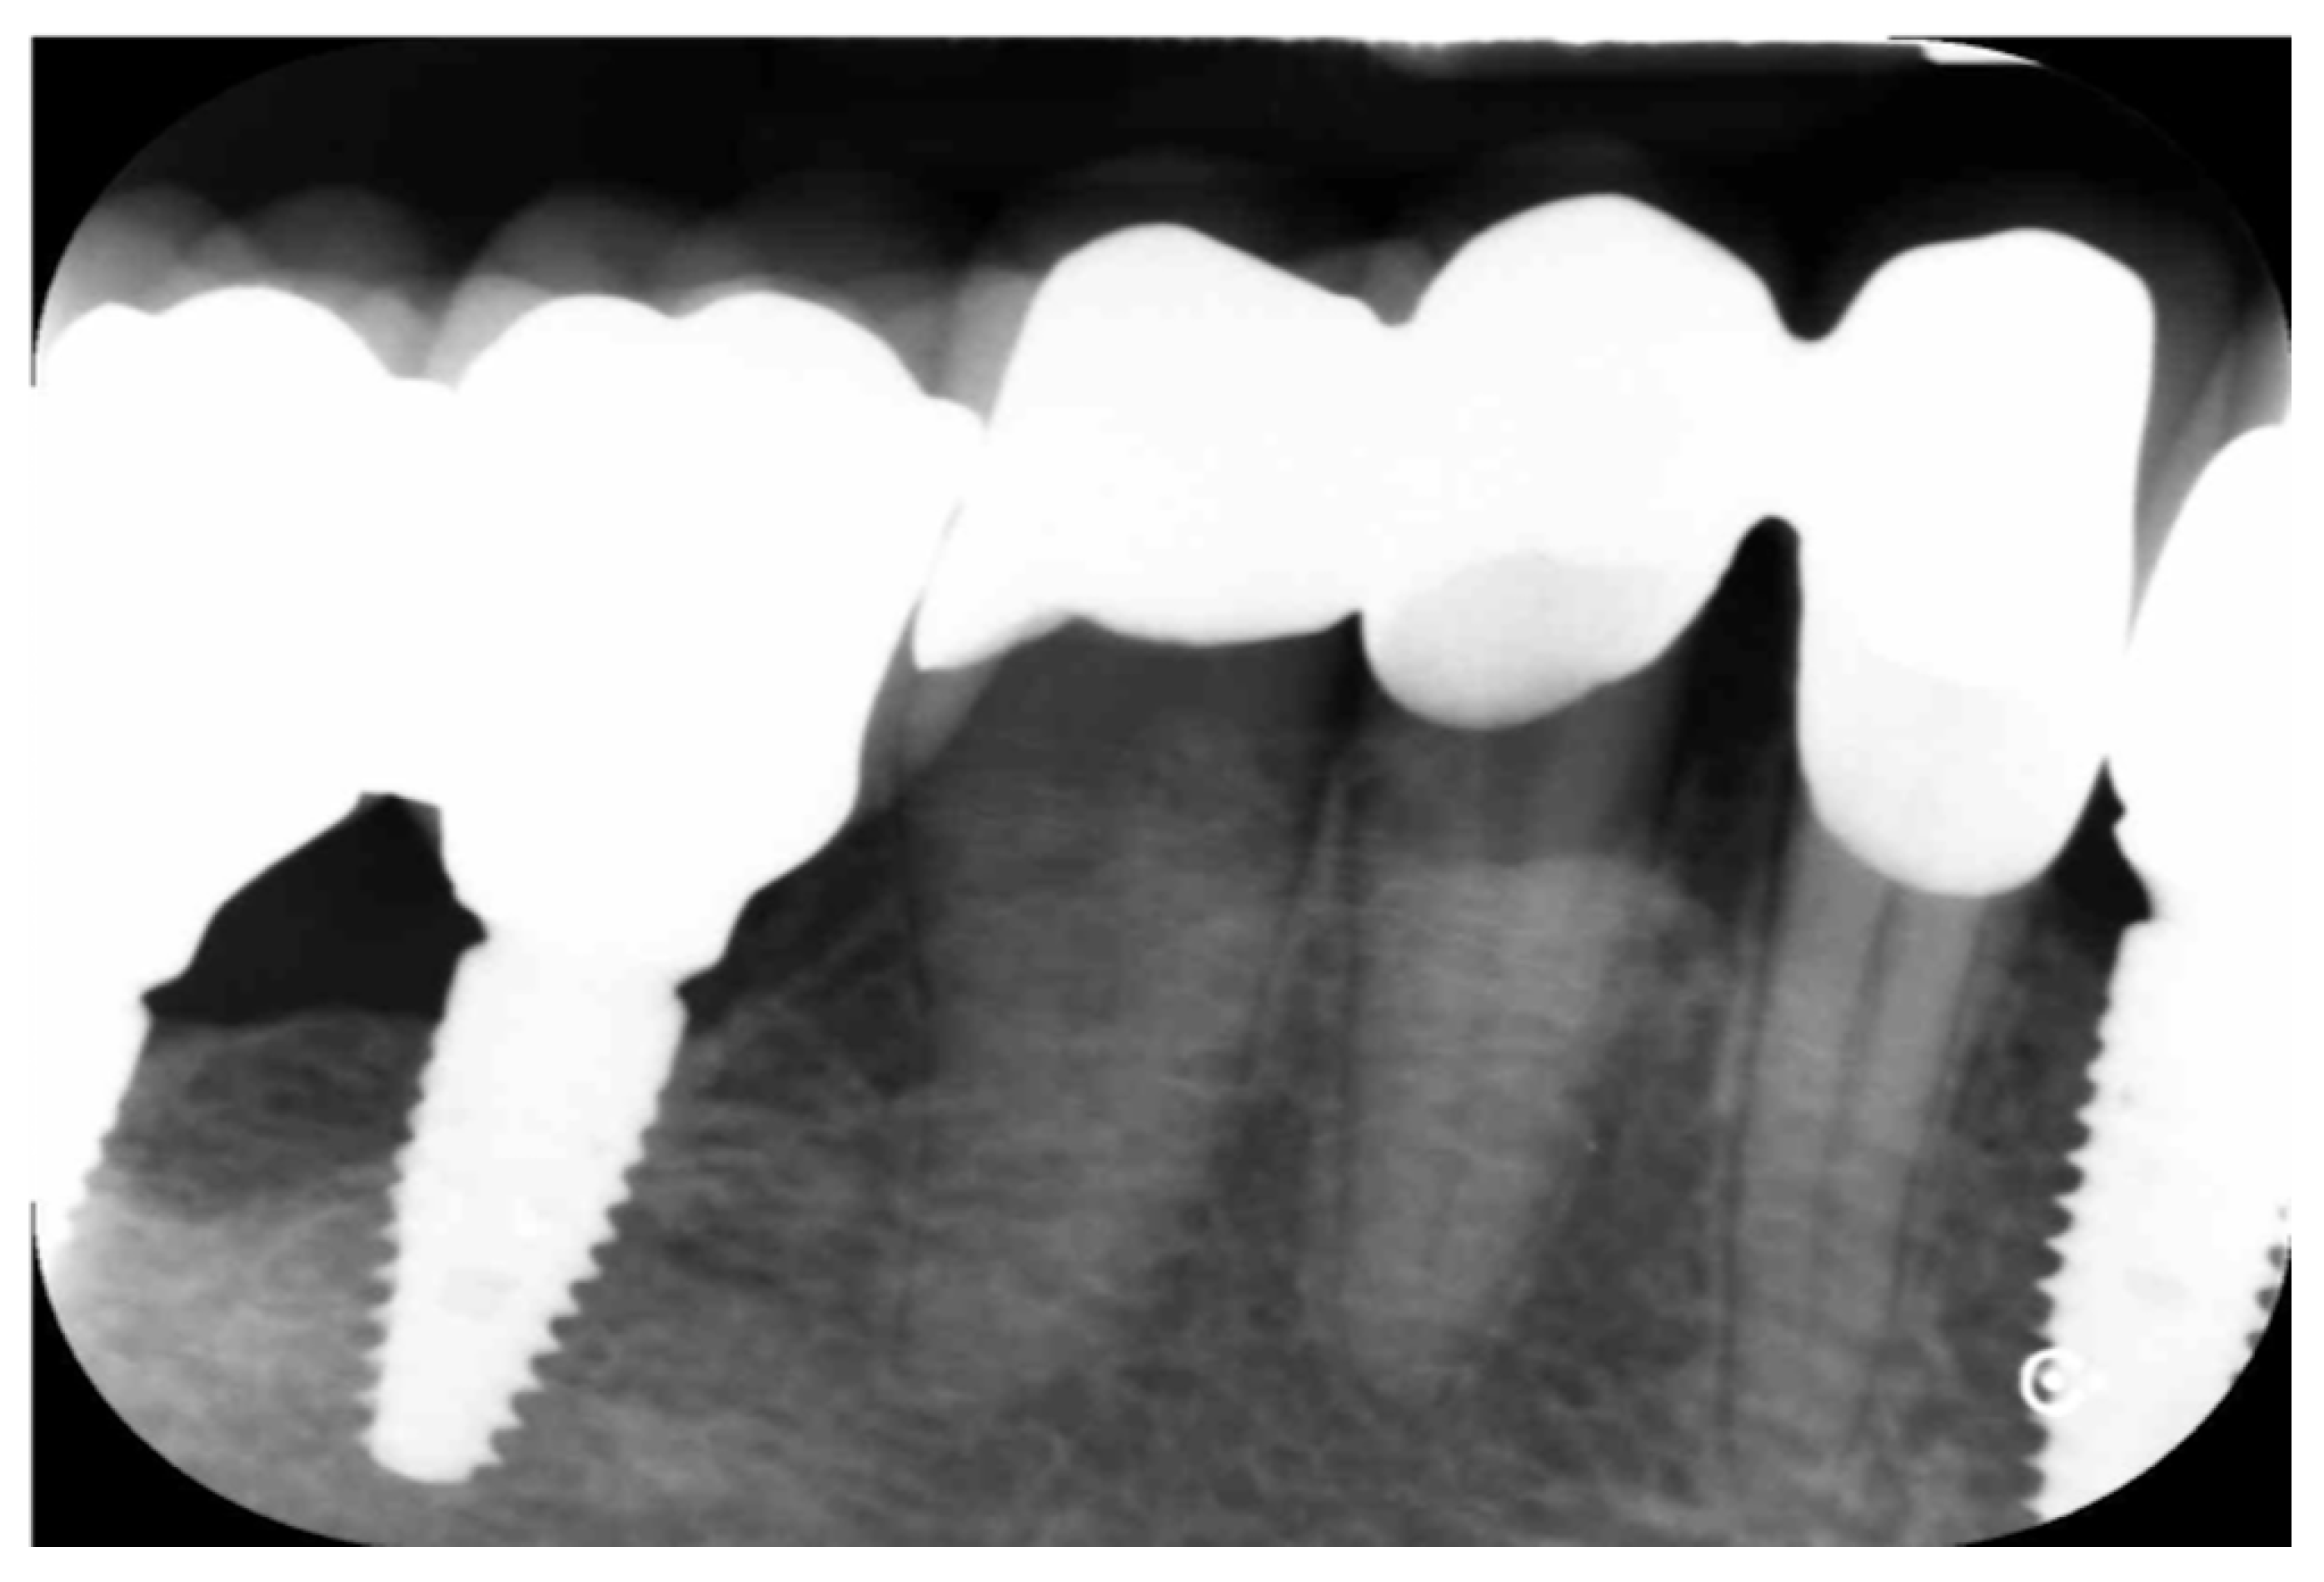

The crowns obtained were judged for clinical fit by a clinician (Figure 17). The rate of compression of sulcular tissues was good. A radiographic control taken after luting showed a proper fit (Figure 18).

Figure 18.

Radiographic control at the time of luting.